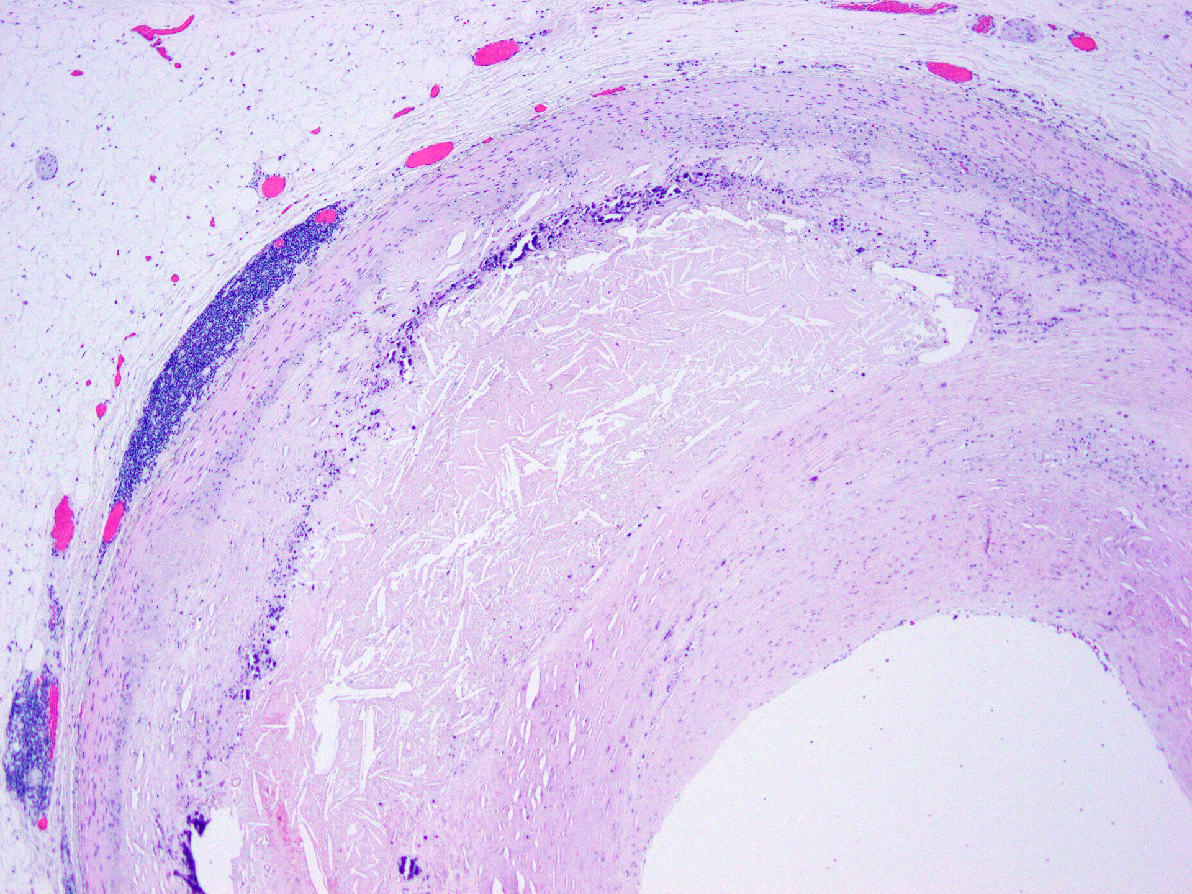

Microscopic (histologic) description

- Fatty streak: subendothelial accumulation of foam cells without necrotic core or fibrous cap

- Fibrous cap atheroma (Am J Med 2009;122:S3):

- Well formed necrotic core with overlying fibrous cap; smooth muscle cells, macrophages, lymphocytes and connective tissue components may be present

- With rupture: luminal thrombus communicates with underlying necrotic core

- With erosion: luminal thrombosis; no communication of thrombosis with necrotic core

- Fibrocalcific plaque: collagen rich plaque, contains large areas of calcification with few inflammatory cells, necrotic core may be present

Microscopic (histologic) images